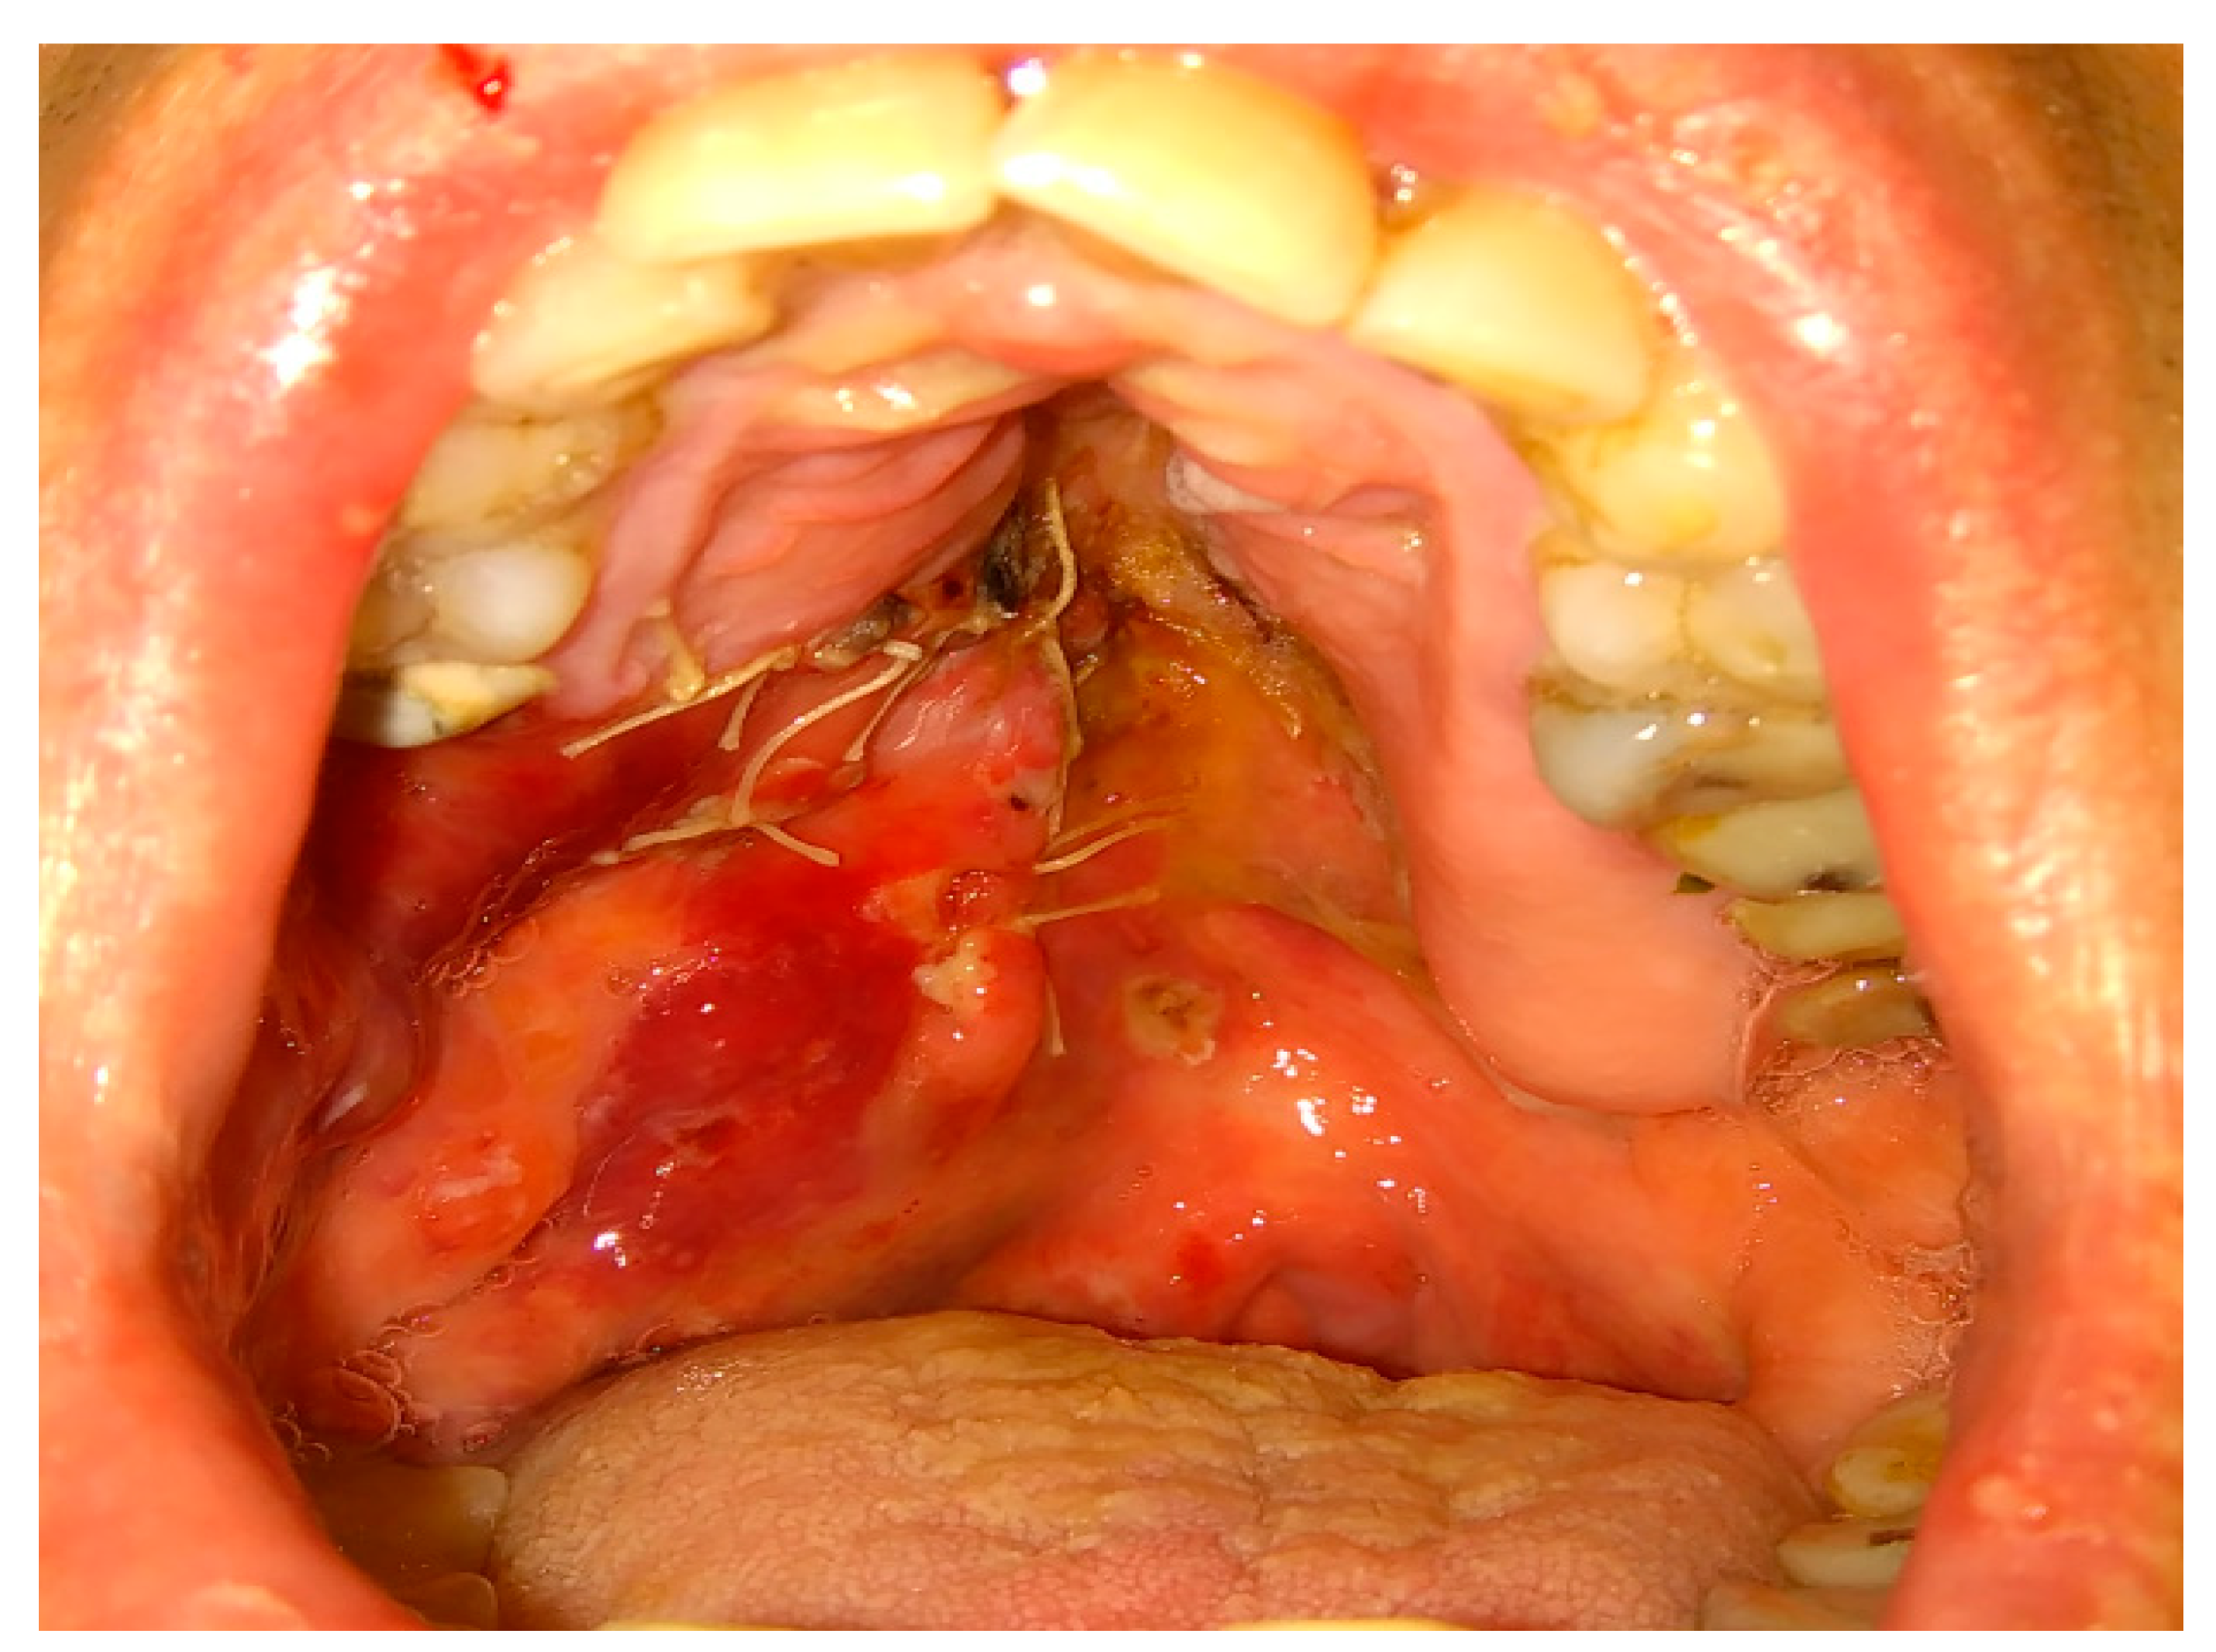

In some special cases, the usage of mucoperiosteal flaps can be insufficient to cover the bone defects. Then, additional usage of the BFP can improve the surgical result (Figure 5, Figure 6, Figure 7 and Figure 8). Various clinical situations can lead to defects in the walls of the paranasal sinuses. Many techniques for defect coverage are known; however, the BFP is considered a very good material for most vertical, horizontal, and combined bone defects in the palate–maxillary area [9,15,16,17,18,19,20,21,22,23,24,25]. The fat pad can be used in different techniques and alterations. Choi et al. presented a case of a patient clinically diagnosed with a dentigerous cyst (DC) associated with a supernumerary tooth in the maxillary sinus. Authors reported their experience with the innovative bilateral pedicled sling BFP flap for intraoral reconstruction after the removal of a larger recurrent DC in the maxillary sinus. The BFP flaps were rotated and covered the alveolar and anterior maxillary defect following cyst enucleation with the Caldwell–Luc procedure [22].

Also, other types of bone inflammation might result in the necessity of some scope of surgical intervention. Oroantral communication formation may be the result of maxillary osteomyelitis of the jaws. One of the possible maxillary inflammations is associated with dental-related factors and results quite often in the formation of secondary findings within the maxillary sinus, like mucous retention cysts or periapical tooth-related inflammations (Figure 5, Figure 6, Figure 7 and Figure 8). The scope of bone inflammation etiology and occurrence requires each surgeon to treat each case individually. Very rarely, in patients with autosomal dominant osteopetrosis (OP), which is a rare metabolic bone disease characterized by a generalized increase in skeletal mass and following increased susceptibility, osteomyelitis of the jaw bones might also occur. In a case reported by Kulyapina, the osteomyelitis of the maxilla resulted in oroantral fistula formation closed surgically with a Bichat fat pad flap [24]. Co-existing findings in the bone, maxillary sinus, and adjacent tissues should be excised simultaneously to avoid unnecessary scaring or tissue adhesions for secondary surgery.

Figure 6. Bichat fat pad mobilization to cover the bone defect and close the oro-antral communication.

Figure 8. Proper suturing of bone defect and closure of the communication between the oral cavity and right maxillary sinus.